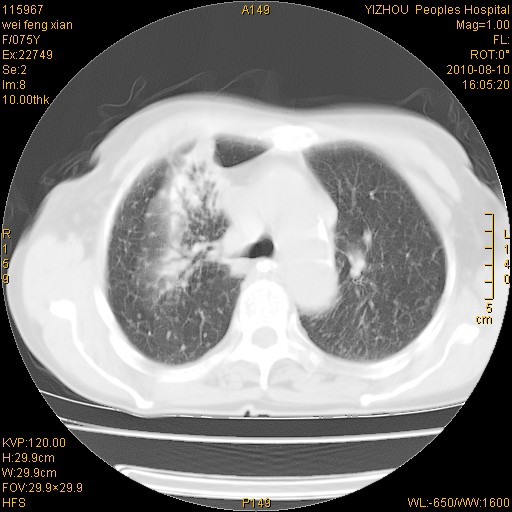

标题: CT28313:两肺弥漫性病变 [打印本页]

标题: CT28313:两肺弥漫性病变

女,75岁,患者反复头昏乏力面色苍白3年,再发10天入院。临床贫血查因。

双肺间质增生并右肺上叶炎性改变,不除外右肺上叶结核病肺内播散

考虑右肺上叶炎症合并双肺结核可能性大,建议上传纵隔窗ct图片。

双肺结核可能性大

考虑尘肺并结核;右上肺支气管扩张!

结核、尘肺、支气管肺泡癌都不能除外

右肺上叶继发性肺结核伴肺内血型播散!

考虑右肺上叶继发性肺结核伴两肺播散。